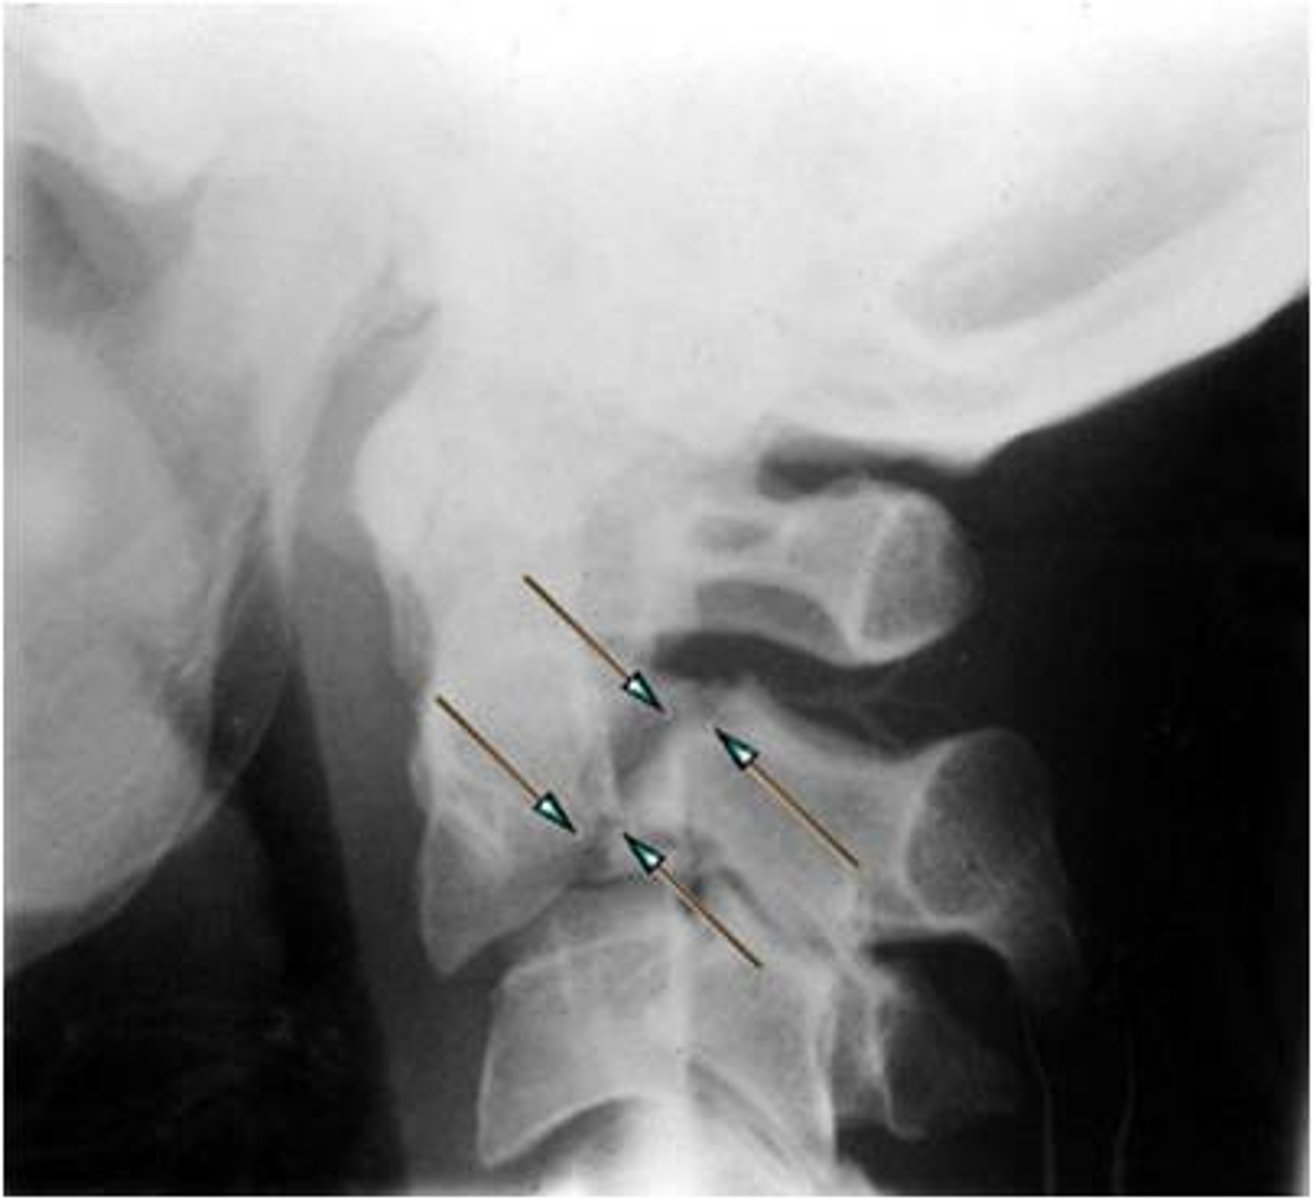

Fracture of the pedicles of C2

Hangman's fx

A hangman's fracture refers to a fracture of which bony structure?

a. symphysis pubis

b. C-7

c. dens

d. gonion

A fracture that occurs through the pedicles of the axis (C2), with or without displacement of C2 or C3, is termed _____ fracture.

a. Odontoid

b. clay shoveler's

c. Jefferson

d. hangman's

d. hangman's fx